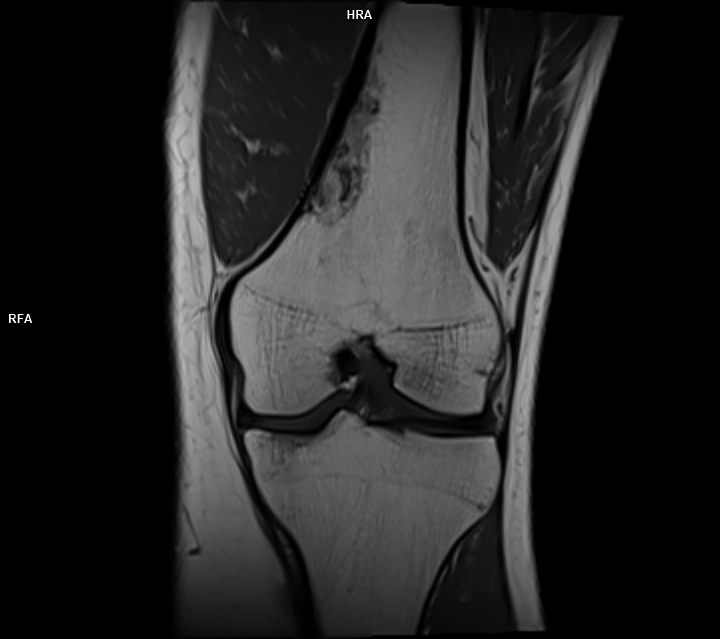

Figura 1: achiziție T1 coronal leziune net delimitată, în contact cu corticala osoasă fără a o întrerupe, conținut lipomatos heterogen